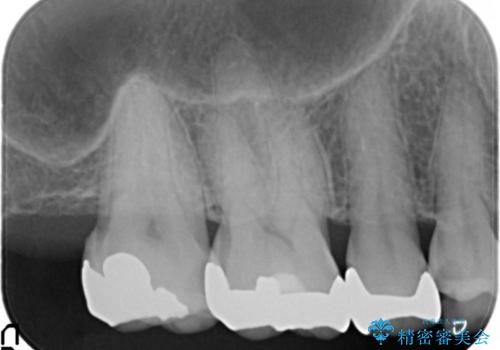

- 虫歯治療を希望して来院。

保険適用の銀色のつめもののやり替えを行いました。

- 30.8万円(右上4567 emaxプレスインレー 7万円x4本)費用は治療当時の料金となります

自由診療のインレーの歯型には、シリコンを使用しています。また、処置時には8倍の拡大鏡を用いて、精密に治療しております。